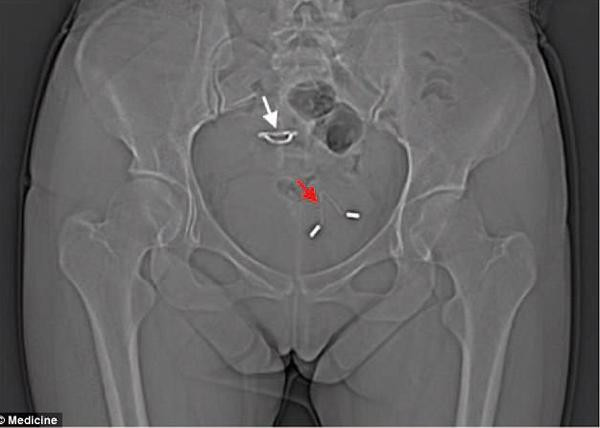

![]() |

| Chiếc vòng tránh thai đâm qua tử cung, chui vào bàng quang người mẹ. |

Lúc này, các bác sĩ thực hiện chụp X-quang và bàng hoàng phát hiện chiếc vòng tránh thai năm nào đã đục thủng tử cung người phụ nữ, đi vào bàng quang rồi gây ra các biến chứng về đường tiết niệu. Những triệu chứng người phụ nữ này gặp phải chắc chắn do lệch vòng tránh thai gây ra nhưng lý do cụ thể vẫn chưa rõ ràng.